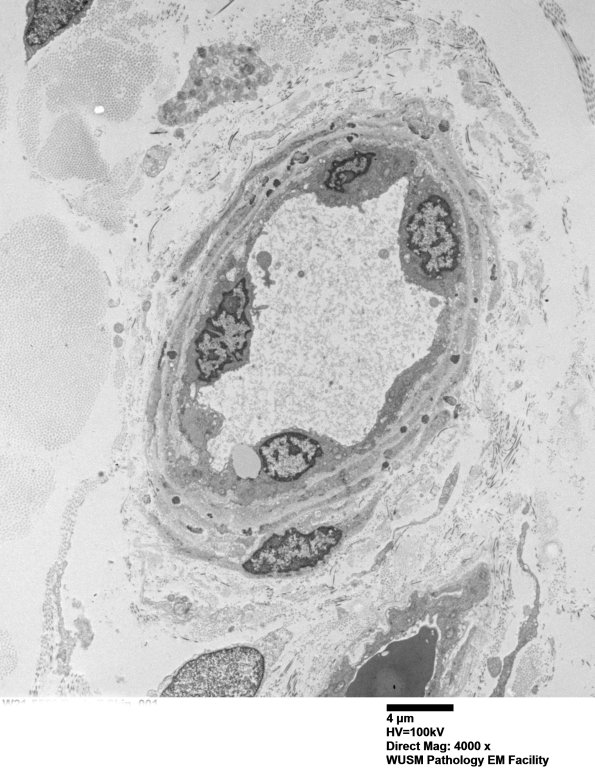

11C4A A small vessel with two muscle layers and multiple GOMs as seen at higher magnification in the subsequent images. (electron micrograph)